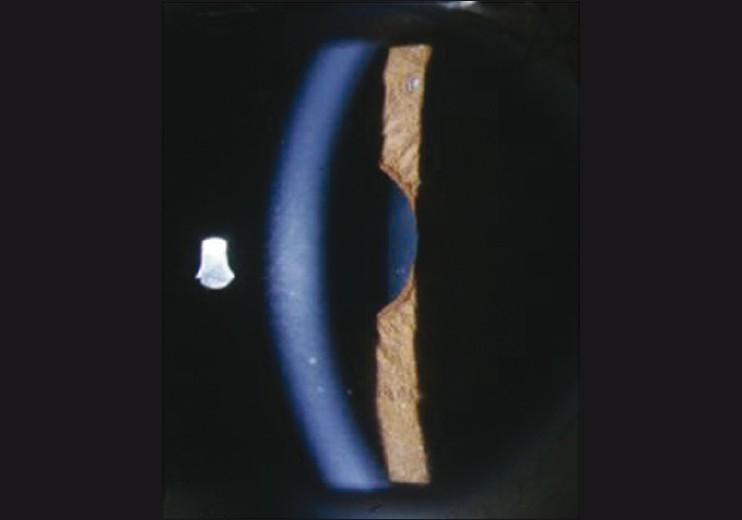

We are reporting a case of bilateral Fuchs' heterochromic iridocyclitis with chikungunya virus infection in the left eye. A 20-year-old female was presented with a past history of fever suggestive of chikungunya with bilateral Fuchs' heterochromic iridocyclitis and complicated cataract. She had a tripod dendritic pattern of keratic precipitates by confocal microscopy in the left eye with a stippled pattern of keratic precipitates in both eyes. The real-time polymerase chain reaction (RT-PCR) assay in the aqueous humor detected 98 copies/ml of chikungunya virus RNA. The patient underwent clear corneal phacoemulsification with in-the-bag intraocular lens implantation in the left eye with a good visual outcome. This is the first report where the presence of chikungunya virus RNA has been associated with a case of bilateral Fuchs' heterochromic iridocyclitis.

我们报告一例左眼感染基孔肯雅病毒的双侧 Fuchs 异色性虹膜睫状体炎。一名 20 岁女性,有发热史,提示为基孔肯雅热,伴双侧 Fuchs 异色性虹膜睫状体炎和并发性白内障。左眼共焦显微镜检查显示三腿树突状角膜后沉着物,双眼呈点状角膜后沉着物。房水中的实时聚合酶链反应 (RT-PCR) 检测到 98 拷贝/ml 的基孔肯雅病毒 RNA。患者左眼行透明角膜超声乳化白内障吸除术并植入囊袋内人工晶状体,视力恢复良好。这是首例报道基孔肯雅病毒 RNA 与双侧 Fuchs 异色性虹膜睫状体炎相关的病例。